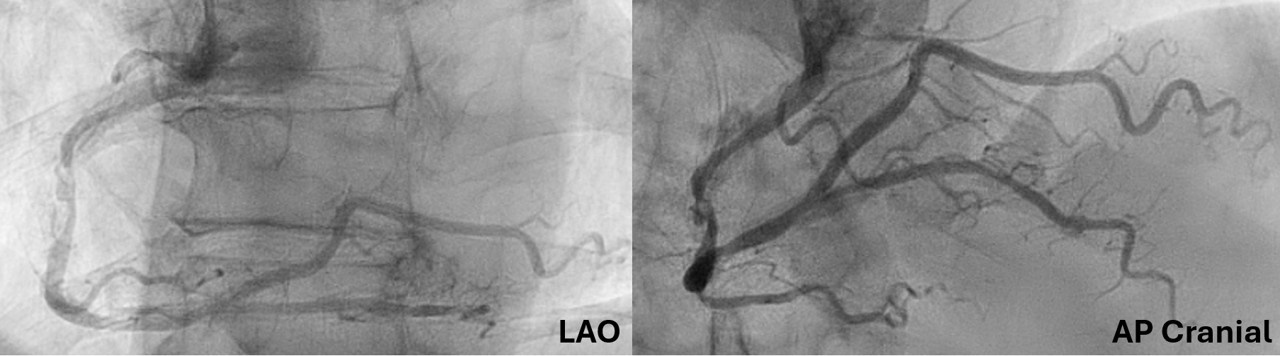

A 65-year-old man presented with unstable angina and calcified right coronary artery (RCA) stenosis (Figure 1) on diagnostic catheterization via radial approach. Percutaneous coronary intervention (PCI) was performed via 7F femoral access using a Judkin’s Right (JR) 4 catheter followed by an Amplatz Left 0.75 guide catheter. Orbital atherectomy (aborted after 6 runs at low-speed because of no-reflow) followed by intravascular lithotripsy (IVL) using a 3.5 mm Shockwave C2+ (Shockwave Medical) was performed. Following this, no equipment could be advanced beyond the mid-RCA calcified nodule (Figure 2).